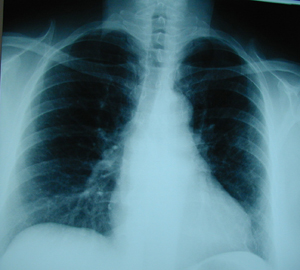

Εικόνα 3

Μετεγχειρητική ακτινογραφία του θώρακος μετά από την αφαίρεση του όγκου.